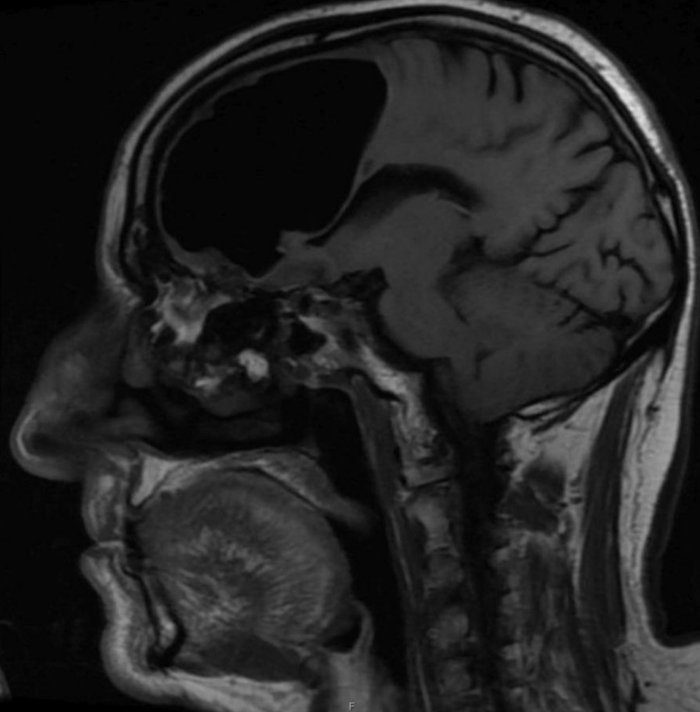

بر اساس گزارش ساینس الرت، تصاویر سی‌تی‌اسکن مغز این بیمار نشان داد، بخش بزرگی از لوب پیشانی راست مغز مرد ناپدید شده‌ است.

نتیجه سی‌تی‌اسکن گیج‌کننده بود، حفره‌ای بزرگ و سیاه به وسعت 9 سانتیمتر در لوب پیشانی سمت راست مرد دیده می‌شد. در مرحله بعدی مغز مرد با دستگاه MRI مورد بررسی قرار گرفت و پزشکان دریافتند ماده مغزی در جمجمه بیمار ناپدید نشده‌است، بلکه درون جمجمه‌اش حفره‌ای از هوا به نام پنوماتوکوئل ایجاد شده‌بود که معمولا در بیمارانی دیده می‌شود که دچار آسیب‌دیدگی صورت یا عفونت تنفسی شده‌اند یا در جمجمه آنها جراحی انجام شده‌ است.